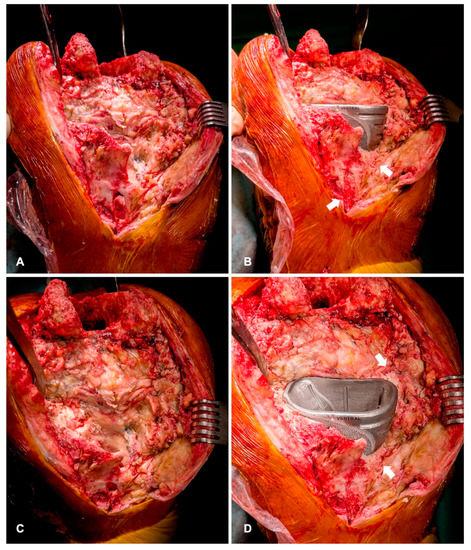

2.4. Planning and Surgical Technique